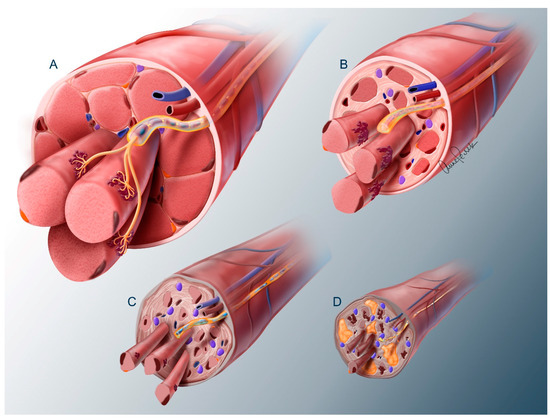

2.1. Nerve Trunk

2.2. Neuromuscular Junction

2.3. Muscle